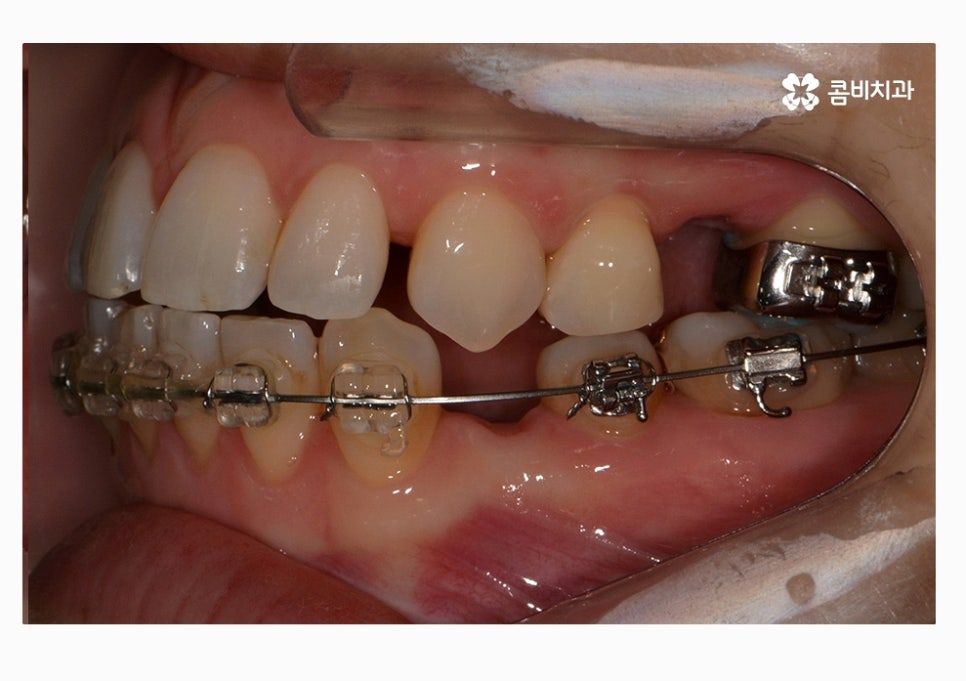

치열 사진을 볼 때 정면보다는 옆모습으로 볼 때

아래 어금니가 위 어금니보다 앞으로 나와있고

앞니 교합이 제대로 맞물리지 않는다는 것이 눈에 띄게 나타나는데

콤비교정은 윗니는 치아의 안쪽에 교정기를 부착하고

아랫니는 치아의 바깥쪽에 장치를 부착하는 방법으로

크게 웃지 않는다면 평소에는 잘 티가 안 나는

심미적으로 우수한 교정 방법이라고 할 수 있어요.

위 환자분의 경우에는 콤비교정의 치료 경과를 보면

아랫니가 정상교합이 되었고 치열도 보다 가지런하게

변화되고 있음을 알 수 있는데요.

위 케이스는 총 1년 9개월 정도의 치료 기간이 소요되었으며,

개개인마다 치료 결과와 기간은 차이가 있을 수 있습니다.